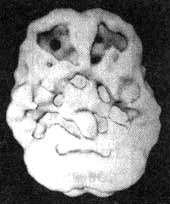

Карл (40 лет) был адвокатом и пришел ко мне после того, как его жена пообещала развестись с ним, если он не прекратит пить. К тому времени он пил уже 25 лет, из них последние 10 лет — много. И если на профессиональной деятельности пьянство Карла стало сказываться только в последнее время, то семейную жизнь оно портило ему долгие годы. Дети перестали приглашать в дом друзей, так как не знали, когда их папа окажется пьяным. Они постоянно за него беспокоились. По поводу пьянства Карл регулярно скандалил с женой. На протяжении нескольких лет у него было высокое давление. Его врач никак не мог подобрать ему эффективное лекарство. Как и большинство страдающих зависимостью, он отрицал, что болен, хотя в конце концов ему уже приходилось спорить со всей семьей. В ходе обследования я назначил Карлу сканирование SPECT. Он согласился на него с большой неохотой. До того он видел в моем кабинете плакаты о воздействии алкоголя на головной мозг. «Если в моем мозгу обнаружатся такие же дырки, не говорите мне об этом, я не хочу этого знать», — попросил он меня перед сканированием. Про себя я подумал: «Лучше бы вы захотели узнать об этом. Иначе у вас не останется мозгов, чтобы вообще хотеть или не хотеть». Как и у многих моих пациентов-алкоголиков, мозг у Карла выглядел сморщенным и намного старше своего биологического возраста. Когда Карл увидел изображение своего мозга, он заплакал. Его жена сидела рядом и положила руку ему на плечо. Я подождал несколько минут, пока впечатление от увиденного немного уляжется, и потом сказал: «Карл, у вас есть выбор. Можете смотреть на собственный мозг и думать: „Я уже испортил себе мозг и потому могу продолжать пить“. Или вы можете сказать себе: „Слава богу, что теперь я это знаю. Слава богу, что моя жена заставила меня обратиться за помощью! Мой мозг имеет возможность вылечиться, если я сейчас прекращу пить“. Карл, алкоголь на самом деле отравляет ваш мозг». Других убеждений Карлу не потребовалось. Он совершенно бросил пить, стал посещать программу девятнадцати шагов и начал заново строить отношения с женой и детьми.

Мозг Карла. Алкогольная зависимость

Трехмерное изображение нижней поверхности. Обратите внимание, что мозг выглядит сморщенным, особенно в области префронтальной коры и височных долей.